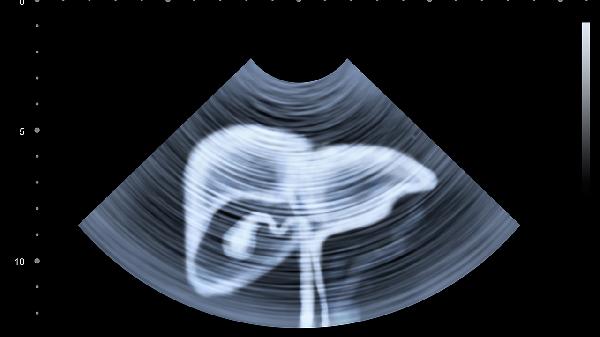

每周檢測(cè)轉(zhuǎn)氨酶、膽紅素等肝功能指標(biāo),超聲檢查觀察肝臟形態(tài)變化。生長發(fā)育曲線監(jiān)測(cè)體重、頭圍增長情況。出現(xiàn)嗜睡、拒食、皮膚瘀斑等惡化癥狀需立即就醫(yī)。